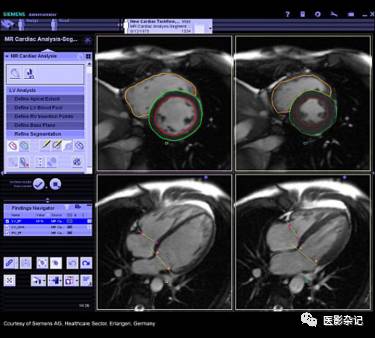

其中,心脏功能学检查是MRI的一项重要应用,其过程大致为:采用电影采集扫描获取并显示心脏MRI心脏动态图像,也就是在一个心跳周期中的多个时相的心脏三维影像;采用手动、半自动或全自动方式勾画心室内外侧壁最大舒张末期和最大收缩末期轮廓,如果能够勾画整个心动周期舒收的每一时相更好;通过勾画的轮廓用心功能分析软件包计算出心室容积、肌块和心功能有关参数绘出心室容积及容积的变化率曲线图;从而进一步根据心室内外心肌壁的轮廓变化来分析及评价心肌厚度,并且以图、表形式显示心肌厚度的变化。

GE CardiacVX 软件包提供电影播放功能,用于辅助查看多断层、多相位MRI影像。GE Cardiac Function Analysis心脏功能分析模块,具备每博输出量(stroke volume)和射血分数(ejection fraction)计算功能,采用半自动方式分割心肌等组织。

Philips MR Cardiac Quantitative Mapping模块提供面向T1、T2和T2*序列的心肌定量测量与映射,用于辅助心肌疾病检测。Philips MR Cardiac Viewing模块则提供面向心功能的心室容积和心肌体积测量等功能,以及心肌运动和厚度变化。

*Philips MR Cardiac Quantitative Mapping

*Philips MR Cardiac Viewing

Siemens Syngo.MR Cardiac 4D Ventricular Function 模块提供基于手工或自动的左右心室容积计算,并内置工作流程向导。

*Siemens Syngo.MR Cardiac 4D Ventricular Function